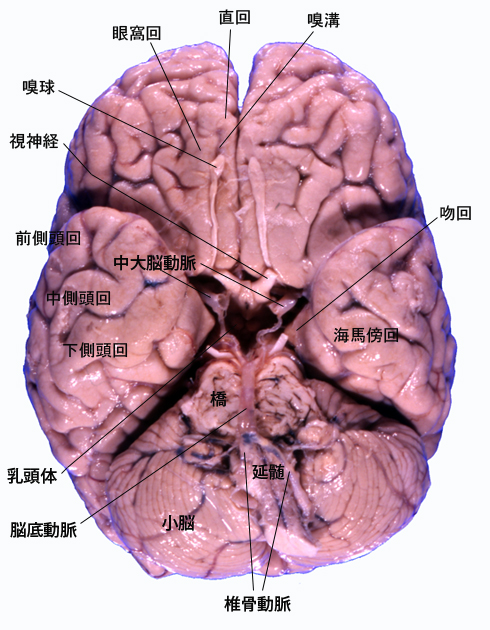

固定脳の切り出し:左図はすでに脳幹を切り取った脳底であるが, 通常は脳幹をつけたまま, 乳頭体をとおるラインで第一の割をいれる。脳幹の付着部分の切除が容易になる。脳幹を傷つけないくらいに少し持ち上げて乳頭体にできるだけ近い部分で脳幹を切り離す。こうすると赤核を含む中脳断面を得ることができる。

乳頭体の前頭断面では深部灰白質の重要構造である視床下核(ルイ体)の最大面がでないことが多いので注意する。視床下核はこの面から5mmないし1cm後方の面。